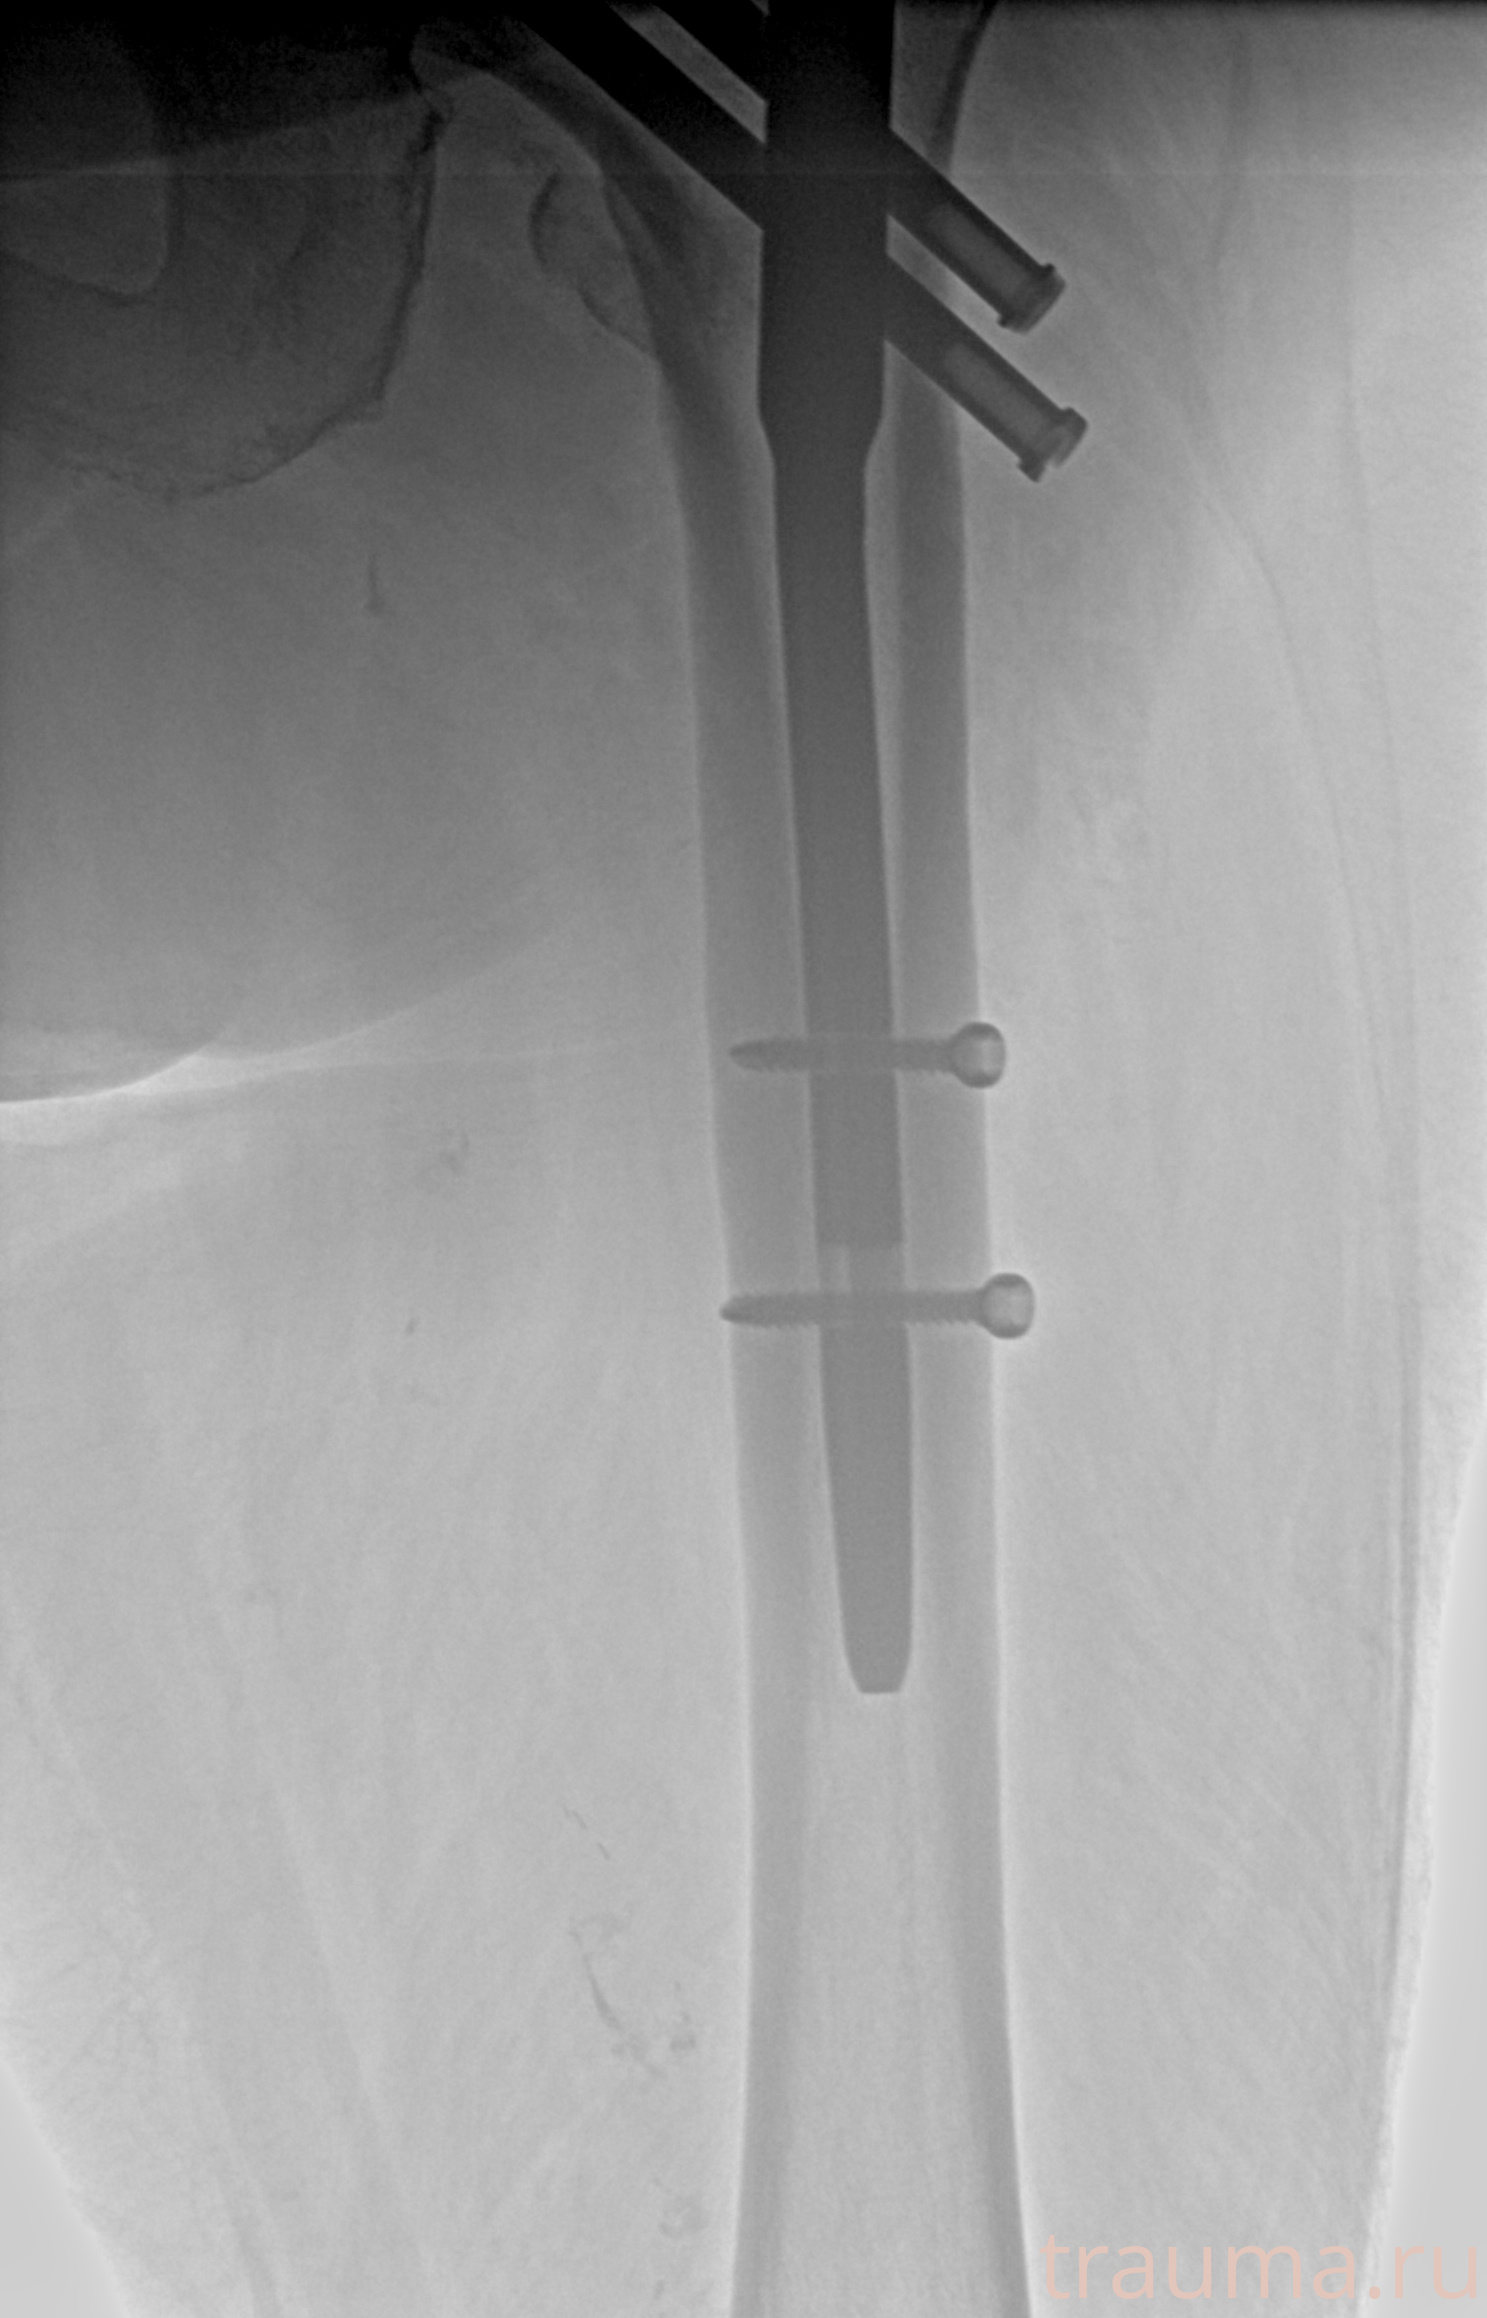

Рентгенограммы

Рентген на дому: по вашему адресу приезжает врач-рентгенолог, травматолог-ортопед с мобильным рентгеновским аппаратом, проводит диагностику травмы или заболевания, делает необходимые рентгенограммы, дает рекомендации по дальнейшему лечению. Получить качественные снимки в домашних условиях возможно благодаря уникальной методике, разработанной МосРентген Центром для института  Склифосовского